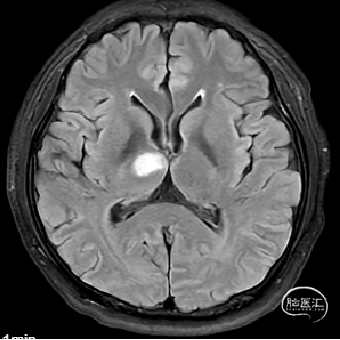

1.右侧大脑脚-右侧丘脑急性脑梗死。

右侧中脑-丘脑可见新发脑梗塞:

CT(CTA)检查提示:右颈内动脉C7段大小约3.6×3.8×3.6mm及基底动脉远端动脉瘤形成大小约9.7×7.6×9.3mm。